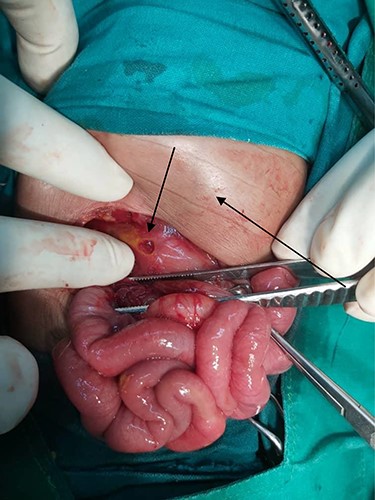

The baby was prepared and taken for an emergency laparotomy whereby intraoperatively, a gastric perforation was found measuring 0.5 by 0.5 cm, circumferential and located on the anterior aspect of the stomach body near the pylorus (Fig. 2). There was also about 50 ml of amber-colored ascites. The perforation was repaired and Grahm’s patch was put, thorough abdominal lavage and the abdomen was closed in layers. Biopsy from the perforation site revealed non-necrotizing mild chronic gastritis, not otherwise specified with ulcerations (Figs 3 and 4).

Photograph showing gastric perforation and abdominal distension (arrows).